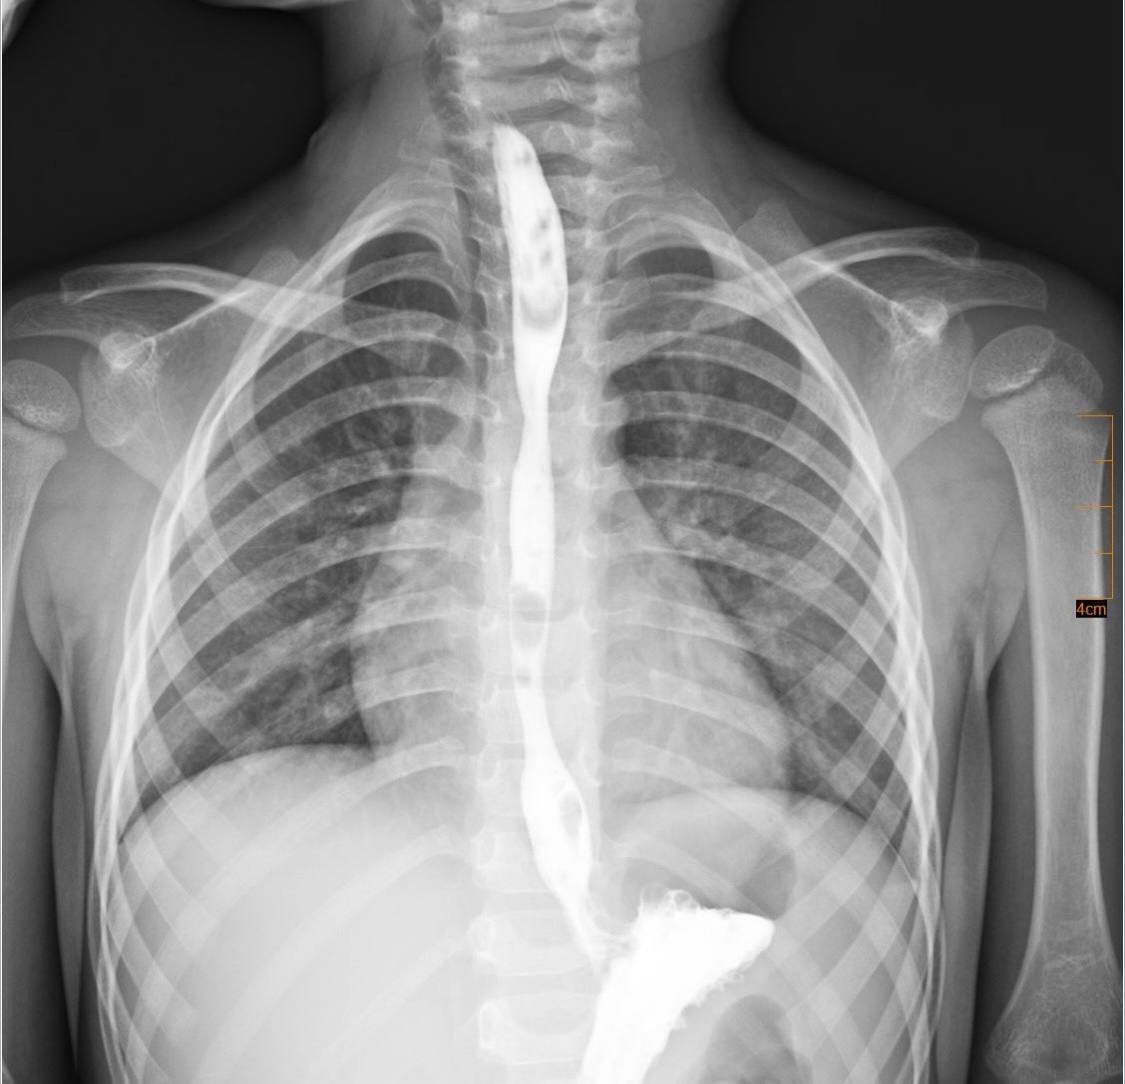

Згодом у дитини розвинувся критичний стеноз стравоходу – значне звуження просвіту, яке повністю унеможливило прийом їжі природним шляхом.

"Після ретельного обговорення мультидисциплінарною командою було ухвалено рішення про проведення серії балонних дилатацій стравоходу – малоінвазивних ендоскопічних втручань, під час яких звужену ділянку поступово розширюють спеціальним балоном без виконання розрізів", – зазначено у повідомленні..